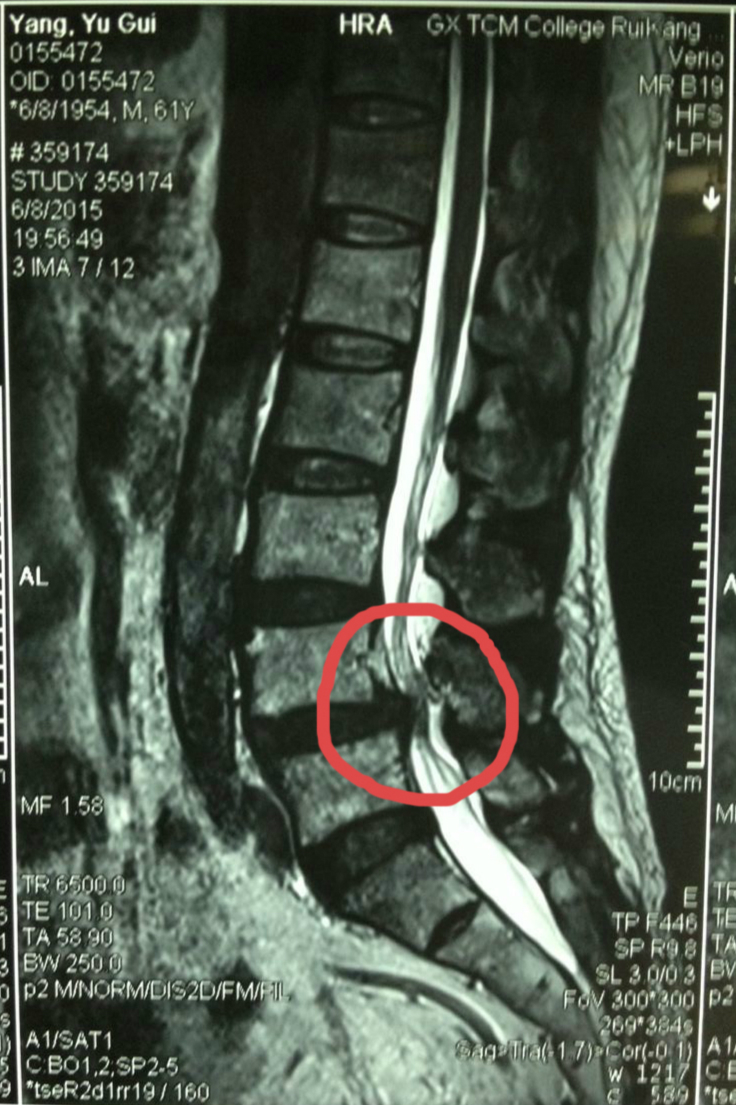

杨老师的主管医生黄保华介绍,杨老师的腰椎间盘突出已导致椎管狭窄,且伴有椎体滑脱。如果实施开放手术,切口会达到10厘米,还需要打钉来固定腰椎,恢复时间至少一个礼拜。现在实施了微创手术,创伤小、恢复快,切口不到一厘米,术后两个小时就能下床走路,大大减轻病人压力。

手术前